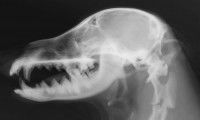

L'examen neurologique permet au vétérinaire de repérer une atteinte nerveuse. Il observe la posture du chien, puis examine attentivement ses déplacements. Il teste ensuite le fonctionnement des nerfs et du cerveau.

Le scanner permet l'examen des structures intracrâniennes.

Enfin, l'IRM, ou imagerie par résonance magnétique, permet d'obtenir des vues en deux ou trois dimensions de l'intérieur du corps du chien.